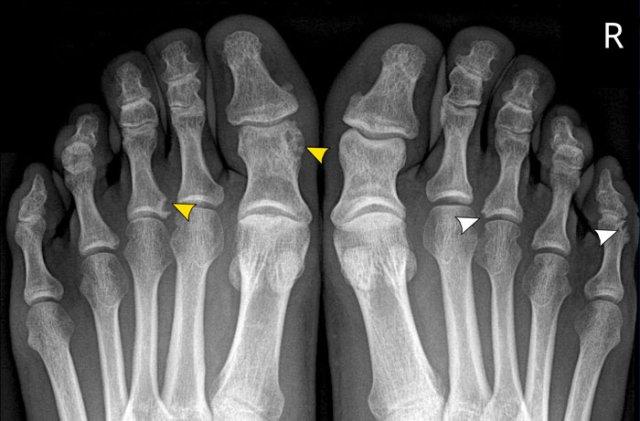

Trong trường hợp viêm khớp dạng thấp này, có hình ảnh bào mòn xương vùng rìa liền kề với hầu hết các khớp bàn ngón chân (MTP) (đầu mũi tên).

Khớp MTP thứ 5 là khớp bị tổn thương thường xuyên nhất trong viêm khớp dạng thấp.

Khi tình trạng bào mòn nặng nề như trong trường hợp này, hình ảnh có thể trông giống biến dạng “bút chì trong cốc” (mũi tên trắng) – dấu hiệu thường gặp trong viêm khớp vảy nến.

Tuy nhiên, phân bố tổn thương chủ yếu ở các khớp MTP và ít ảnh hưởng đến các khớp liên đốt là dấu hiệu gợi ý đây là trường hợp viêm khớp dạng thấp.

A. Biến dạng bút chì trong cốc tại ngón chân thứ 1 và thứ 5.

B. Tiêu xương đầu ngón (acro-osteolysis) với tiêu xương chỏm đốt ngón xa của ngón 2-4 và 5.

Có bào mòn xương tại khớp bàn ngón chân (MTP) 2 và 3.